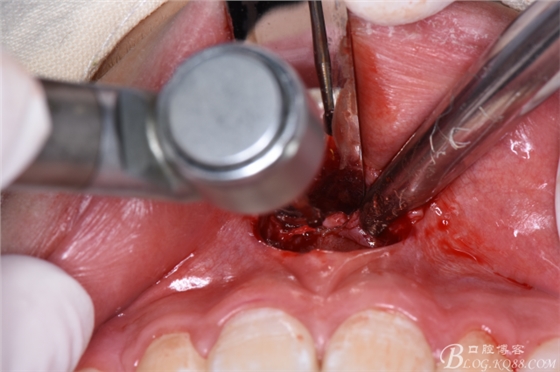

圖10.暴露出11、21之間的倒置多生牙牙冠

圖11.暴露出整個多生牙牙冠

圖12.將暴露多生牙牙冠分成牙根河牙冠兩部分